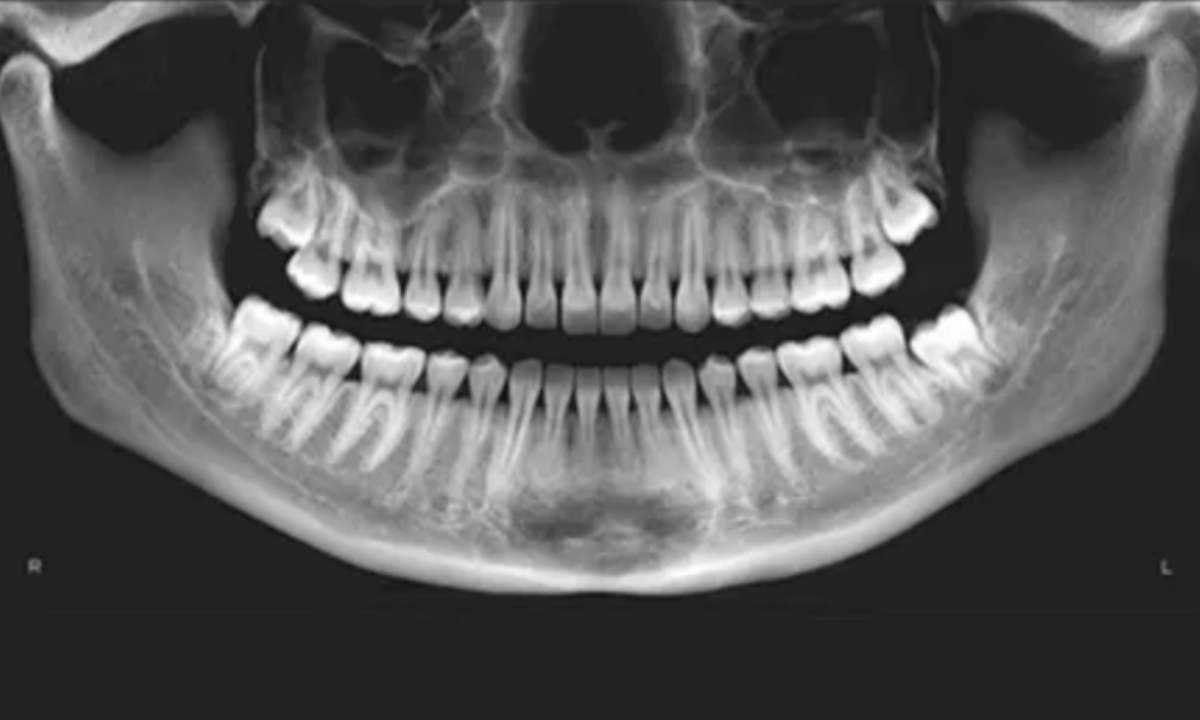

In clinical dentistry, an OPG, formally known as an Orthopantomogram, is a highly specialized extraoral radiological scan. Unlike standard intraoral X-rays, where the radiographic sensor is placed directly inside the patient’s mouth, the OPG utilizes advanced panoramic tomography.

This specific imaging modality allows the diagnostic team to capture the entire maxillofacial structure, encompassing the complete upper maxillary arch, the lower mandibular arch, all present dentition, and the complex temporomandibular joints, within a single continuous two-dimensional image.

A panoramic dental scan that provides a single, complete image of the entire oral region, including the upper and lower teeth, jawbones, wisdom teeth, temporomandibular joints, and surrounding sinus areas, offering a broader view than standard dental X-rays that capture only a few teeth at a time.

When a maxillofacial radiologist or dental surgeon reviews an OPG X-ray image, they are evaluating a flattened, two-dimensional projection of a complex, curved three-dimensional structure.

The resulting digital radiograph presents the entire lower facial skeleton as a continuous, wide U shape. The clinician does not simply look at the teeth. Instead, they systematically analyze several distinct anatomical zones to formulate a comprehensive, highly accurate diagnosis.